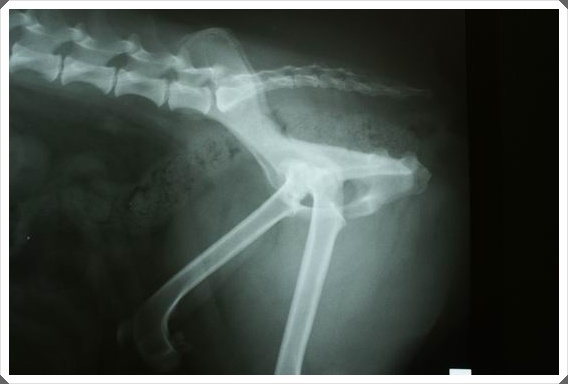

醫生覺得還是得拍一次正確的x光片,才知道是否有脫臼、拉傷...

終於緊張的時刻要來到了...共拍了二張x光片...聽說完整的報告會mail到信箱給我...

Dr.李說,從這張x光片看的出來,兩隻腳都有髖關節,

左腳是中度,而右腳因為扭到脫臼,所以已經算是重度了...包覆的沒那麼完整了...